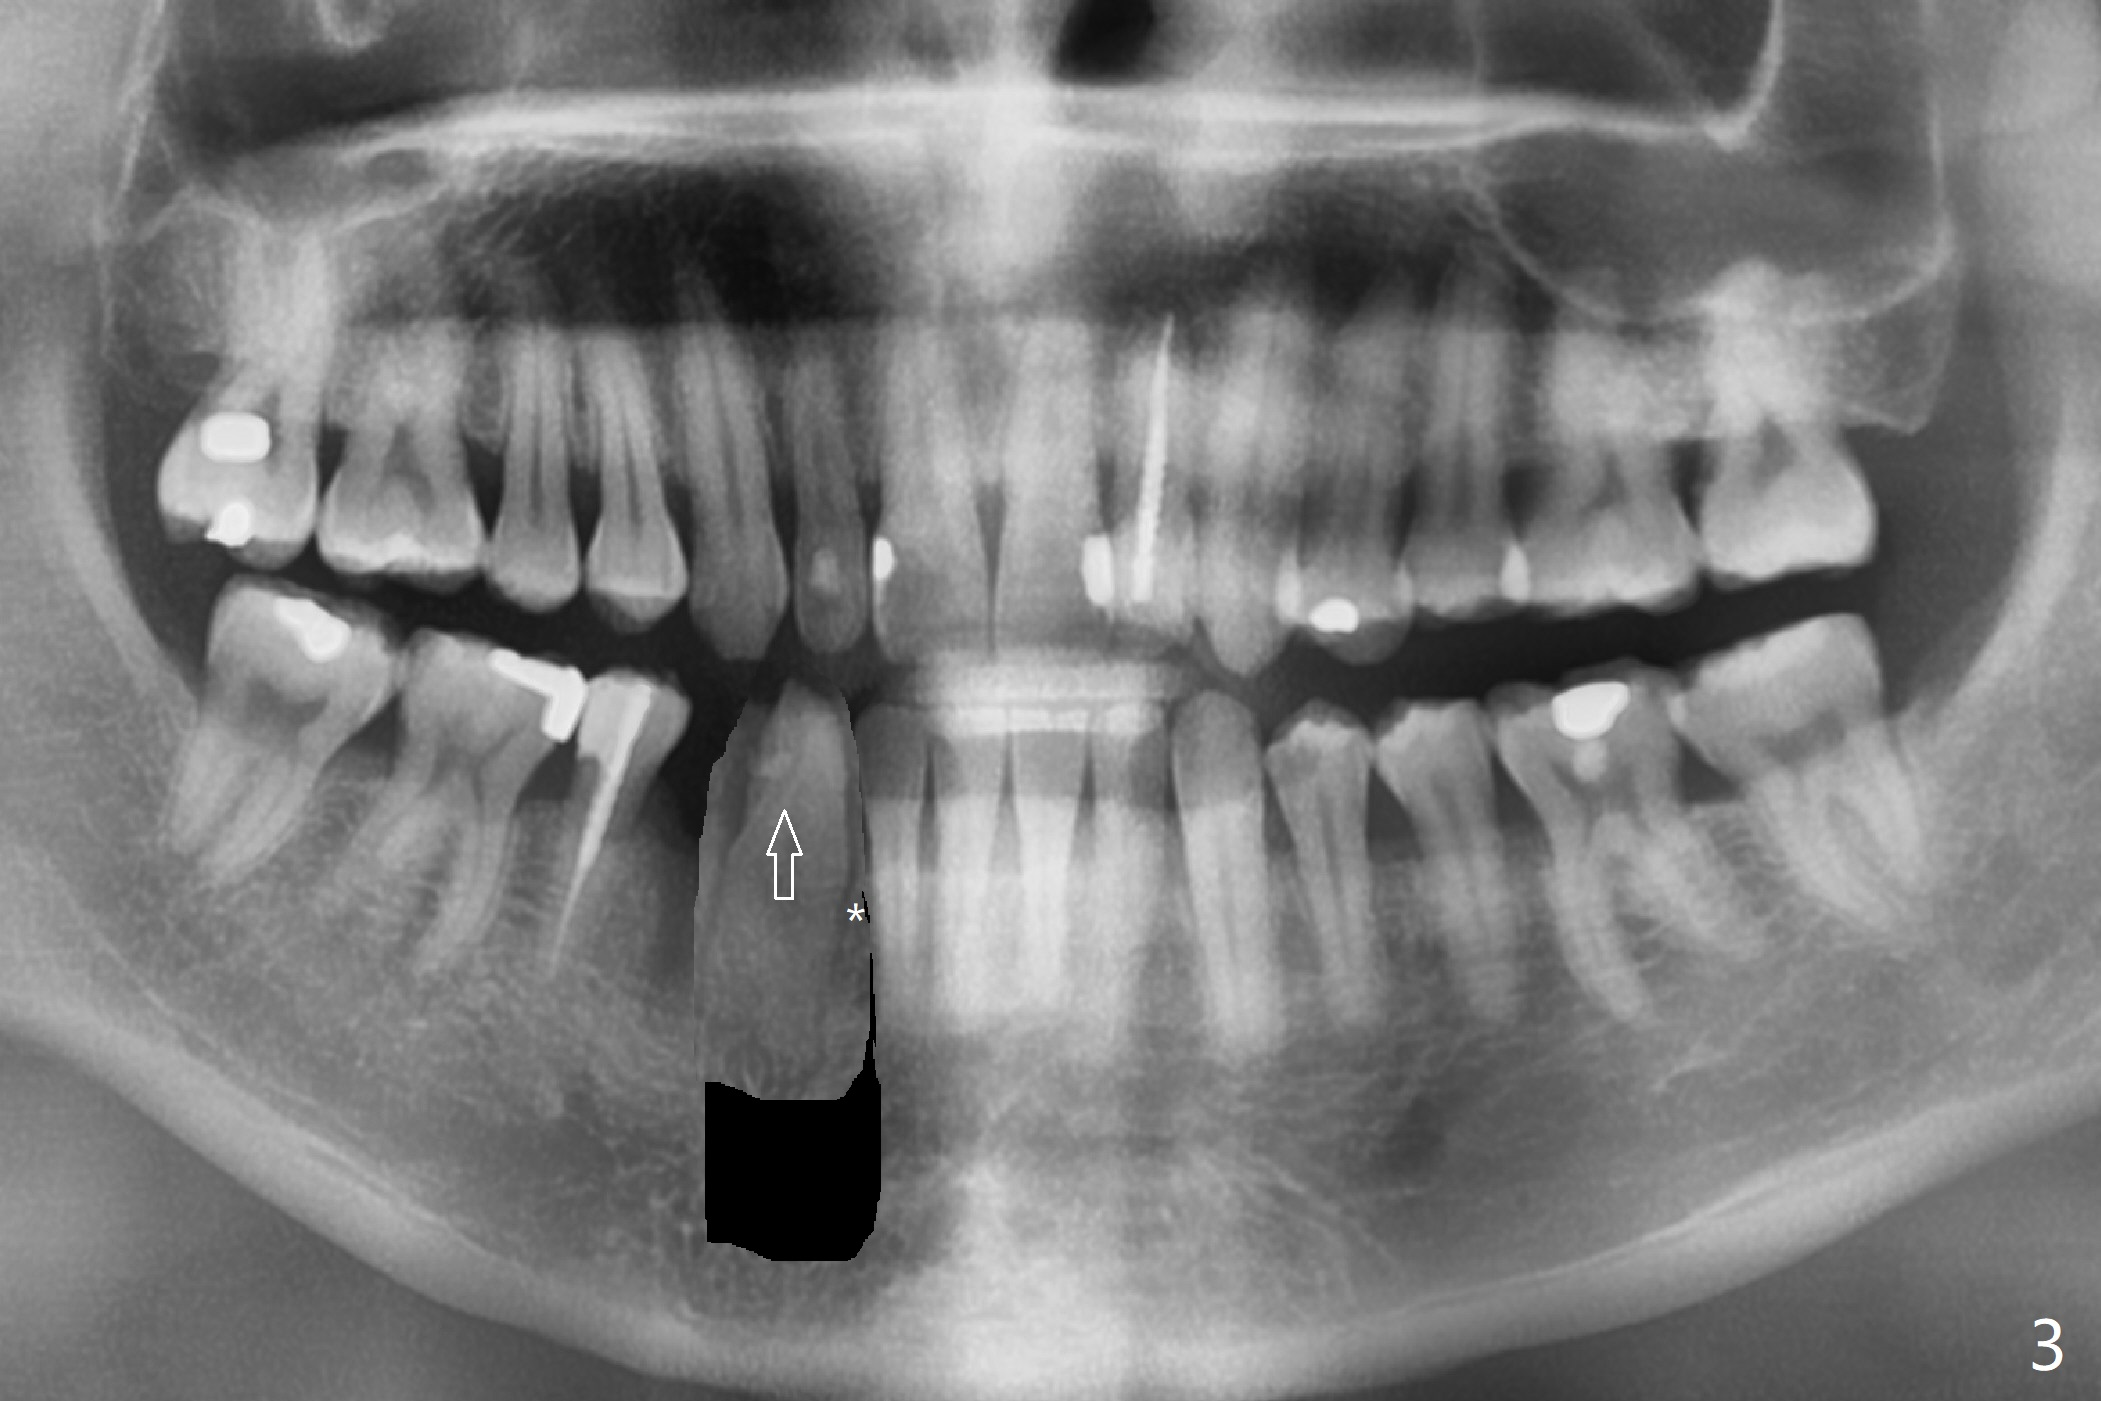

A 30-year-old man requests orthodontic extrusion of the impacted lower right canine and implant at the next site (Fig.1). Since the canine rotates with wider mesiodistal width of the crown (Fig.2 red line), the implant should be smaller and placed distal (Fig.2 red arrow). The extrusion will gain the bone to the distal surface of the lateral incisor (Fig.2, 3*). In fact the tooth #27 is malformed in that the root is split (Fig.4, as compared to the tooth #22 (Fig.5)). Surgical guide will be used for precision.